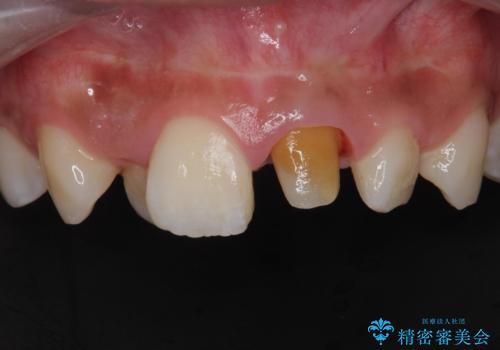

- 前歯の見た目が気になるとの事で来院。

根の治療のやりかえは希望されなかったので土台だけやりかえを行い、ジルコニアクラウンで治療を行いました。

- ジルコニアクラウンスタンダード・仮歯・ファイバーコア 18.7万円費用は治療当時の料金となります